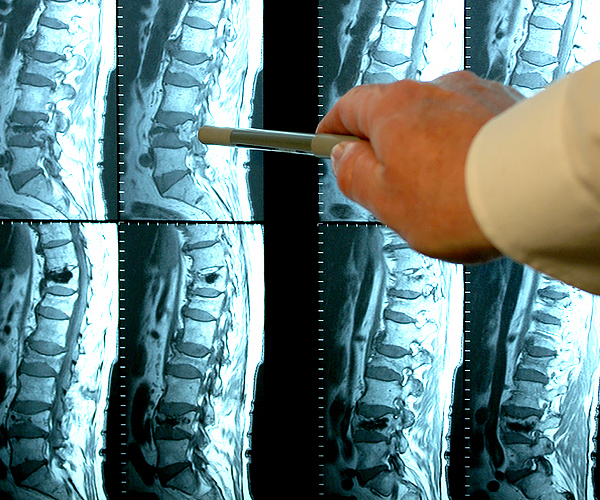

Femme de 54 ans. Son articulation est entièrement restaurée. La durée du traitement : 14 jours :

Traitement de l'articulation de la hanche d'un patient âgé de 44 ans. La douleur atroce qui a torturé le patient pendant 2 ans, a été complètement guérie :

Restauration de l'articulation du coude. Patiente, 31 ans. Durée du traitement par la Marukaya Cream : 12 jours. Son articulation est entièrement restaurée :